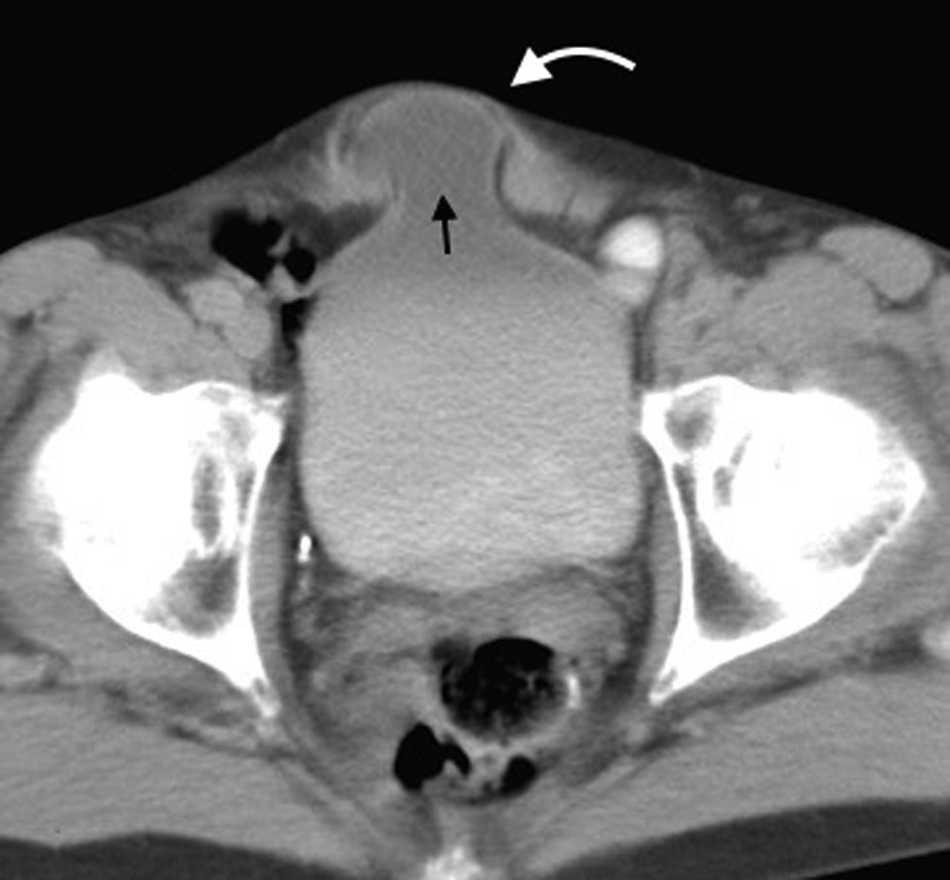

Hernia obturatriz

Su diagnástico clínico es difícil porque su incidencia es infrecuente, su localizaci??n profunda y tiene pocos signos o s??ntomas espec??ficos, como los relacionados con la compresi??n del nervio obturador (signo de Howship-Rombeng)10. El foramen obturador se conforma por la continuidad de los huesos isqui??ticos y p??bicos, y est?? cubierto por la membrana obturatriz, excepto en el receso anterosuperior donde es perforada por la arteria, la vena y el nervio obturador, que viajan a lo largo del t??nel de 2-3 cm formado por los m??sculos obturadores internos y externos. A trav??s de este defecto, se produce la hernia peritoneal11.

Es m??s com??n en mujeres mult??paras de edad avanzada debido a la debilidad generada en el piso p??lvico, aunque tambi??n se ve en pacientes con aumento de la presi??n abdominal y ancianos debilitados1.

Su diagn??stico espec??fico se puede hacer si en la TCMD de pelvis se visualiza el intestino herniado entre los m??sculos pect??neo y obturador externo con obstrucci??n del intestino delgado sin una causa aparente3 (fig. 4).